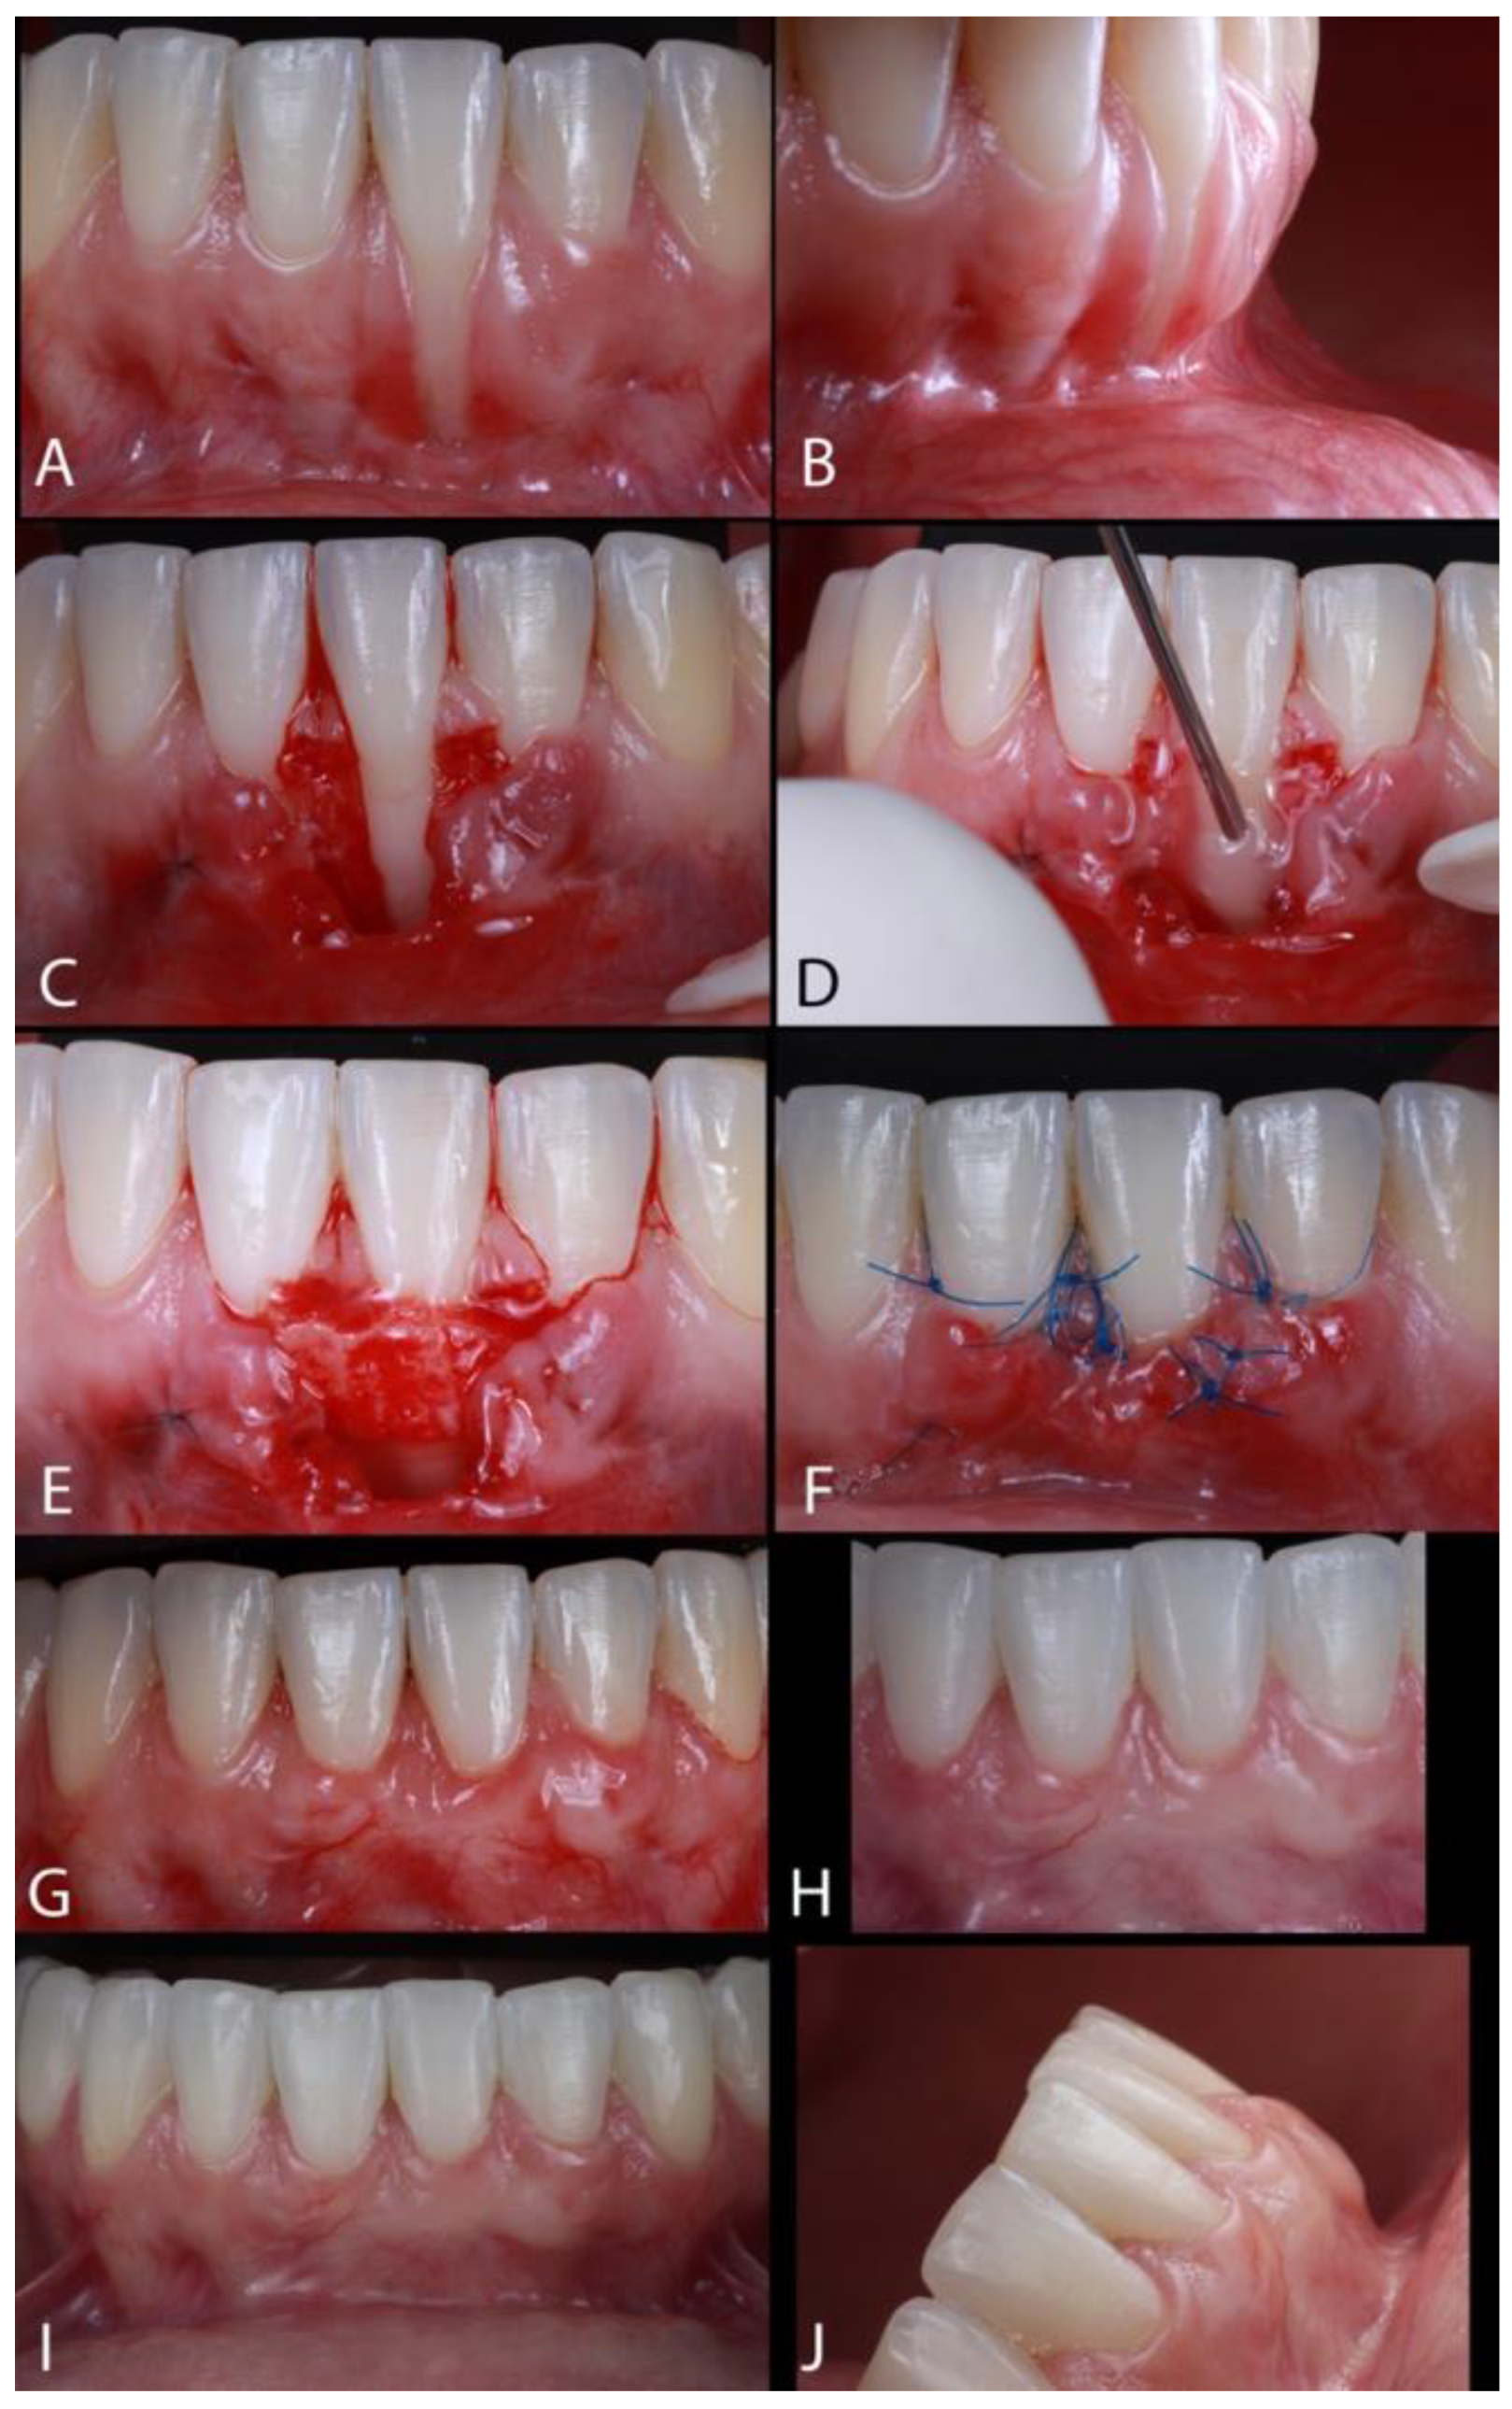

The Treatment of Gingival Recessions in the Lower Anterior Region Associated with the Use/Absence of Lingual-Fixed Orthodontics Retainers: Three Case Reports Using the Laterally Closed Tunnel Technique and Parallel Incision Methods

- Sculean, A.; Allen, E.P. The Laterally Closed Tunnel for the Treatment of Deep Isolated Mandibular Recessions: Surgical Technique and a Report of 24 Cases. Int. J. Periodontics Restor. Dent. 2018, 38, 479–487. [Google Scholar] [CrossRef] [PubMed]

- Kahn, S.; Araujo, I.T.E.; Dias, A.T.; Souza, A.B.; Chambrone, L.; Fernandes, G.V.O. Histologic and histomorphometric analysis of connective tissue grafts harvested by the parallel incision method: A pilot randomized controlled trial comparing macro- and microsurgical approaches. Quint. Int. 2021, 52, 2021. [Google Scholar]

2. Materials and Methods

3. Results